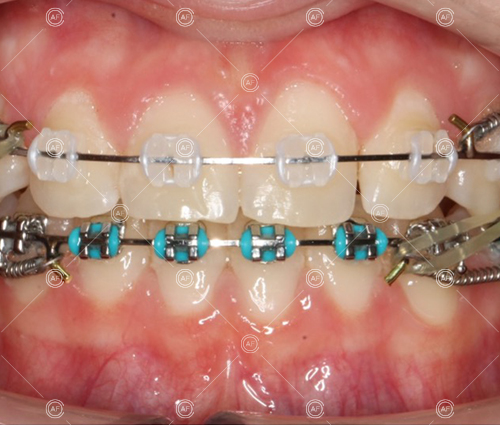

This patient (MH) began her active orthodontic treatment in October 2019 at almost 13 years old. She was unhappy with the appearance of her upper and lower teeth, and especially concerned about the unsightly nature of the high and buccally positioned upper left canine.

about this case…MH presented with class 1 incisors on the class 1 skeletal base with a slightly increased vertical proportion. She had severe crowding in the upper arch and moderate crowding in the lower. Due to the crowding in the lower arch, the lower centre line was off to the left by 2mm.

Buccal segments were essentially class 1 on the right hand side and a full unit class 2 on the left. This is due to buccal exclusion of the upper left 3 and mesial drift of the upper buccal segment.